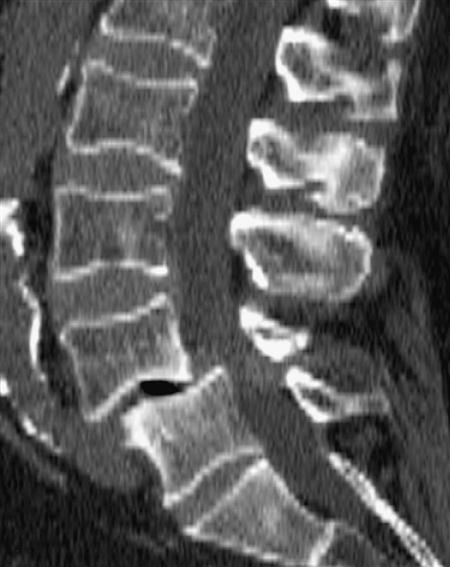

A CT scan may be used to delineate a fracture or to show the presence of spinal stenosis caused by protrusion or a tumor, or if a bony abnormality is suspected256 (Figures 9-116 through 9-119). As with plain x-rays, results must be correlated with clinical findings, because the anatomical changes seen are often unassociated with the patient's symptoms.255,264,265 This technique provides an axial projection of the spine, showing the anatomy of not only the spine but also the paravertebral muscles, vascular structures, and organs of the body cavity. In doing so, it shows more precisely the relation among the intervertebral discs, spinal canal, facet joints, and intervertebral foramina. It may be used to evaluate spinal stenosis, the shape of the spinal canal, epidural scarring (after surgery), facet joint arthritis, tumors, and trauma.124,266,267 It may be used in conjunction with a water-soluble contrast medium (computer-assisted myelography) to further delineate the structures.